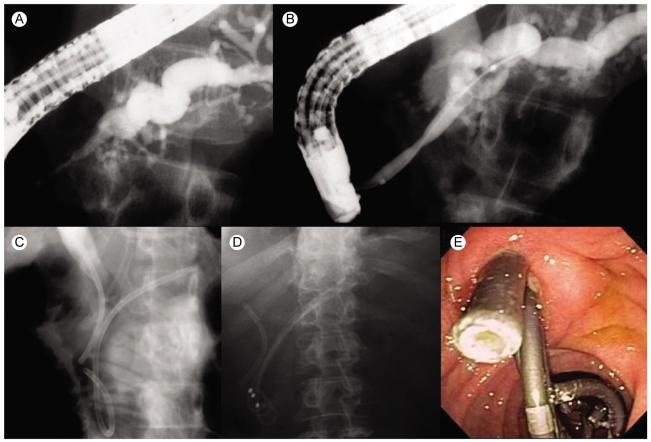

Update on endoscopic treatment of chronic pancreatitis.

Endoscopic therapy has been increasingly recognized as the effective therapy in selected patients with chronic pancreatitis. Utility of endotherapy in various conditions occurring in chronic pancreatitis is discussed. Its efficacy, limitations, and alternatives are addressed. For the best management of these complex entities, a multidisciplinary approach involving expertise in all pancreatic specialties is essential to achieve the goal.

内镜治疗已越来越被认为是慢性胰腺炎特定患者的有效治疗方法。本文讨论了内镜治疗在慢性胰腺炎各种情况下的应用。阐述了其疗效、局限性及替代方案。对于这些复杂疾病的最佳管理,多学科方法(包括所有胰腺专业的专业知识)对于实现目标至关重要。